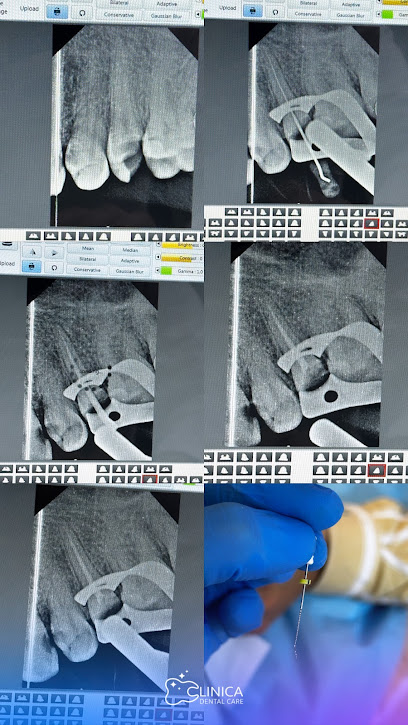

عيادة كلينكا لطب وتجميل الأسنان

عيادة كلينكا هي وجهتك المثالية لطب وتجميل الأسنان. تقدم العيادة خدمات طبية عالية الجودة بواسطة أطباء أسنان محترفين ومتخصصين. سواء كنت بحاجة إلى علاجات تقويم الأسنان، زراعة الأسنان، تبييض الأسنان، أو أي خدمة أخرى، فإن فريق عمل كلينكا مستعد لخدمتك. يُمكنك التواصل معهم عبر الهاتف على الرقم: +9647853907853.